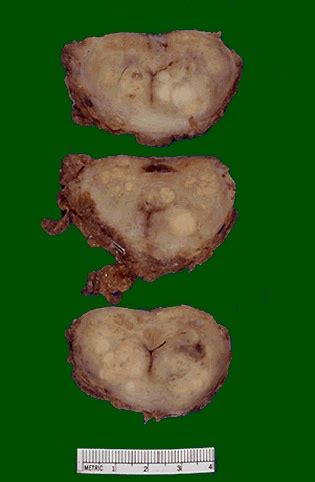

How To Know If You've Got Prostate Cancer - Coughs are a significant diagnostic tool, but how do you ... - You don't need to try and remember all the signs and symptoms of cancer, but we have listed some key ones to give you an idea of the kind of things to be aware of.. In that time 77 (17%) of the men in the study died but only 5 (1%) died from prostate cancer. Examine your diet as a factor. When prostate cancer spreads, it's common for cancer cells to go to your lymph nodes and then move to more areas of your body. An operation was out of the question, he has received radium treatment and is on the hormone implant. Sometimes symptoms are linked to certain cancer types.

If the cancer is small and limited to the prostate gland, the tumor itself may be surgically removed. Men age 50 and older run a greater risk. If signs are pointing to prostate cancer, tests will be done. For the test, a clinician takes a sample of your blood and sends it to a lab for analysis. If bladder cancer is found, certain features of the cancer cells help the doctor know how best to treat it:

What's the Real #MilkTruth? PETA Pours Dairy Industry a ... from www.peta.org I was one of the sheep. I know exactly how you feel because my husband has prostate cancer. Either it had gotten advanced enough to cause symptoms like back pain or urinary. Examine your diet as a factor. The changes tell the cells to grow and divide more rapidly than normal cells do. A biopsy of prostate tissue also may be required to confirm diagnosis. If you've received a prostate cancer diagnosis, here's what you need to know. I just went in for the program and did the biopsy.

He had a psa of 18.5 with gleeson 4/5 = 9. If signs are pointing to prostate cancer, tests will be done. Prostate cancer usually grows very slowly, and finding and treating it before symptoms occur may not improve men's health. Though he says that prostate can. The survival rate for all stages of prostate cancer is about 98%, the acs reports. The abnormal cells continue living, when other cells would die. If you're told you have cancer but it hasn't. If your cancer was diagnosed through regular screening, that's an extra reason to be upbeat: We still recommend you to diagnose prostate cancer by means of psa (prostate specific antigen) test; Some people find it easier to be open with someone they don't know well. Some symptoms of prostate cancer can be caused by other conditions, so you'll need an examination. A biopsy of prostate tissue also may be required to confirm diagnosis. Treatment for prostate cancer depends on the extent of the disease.